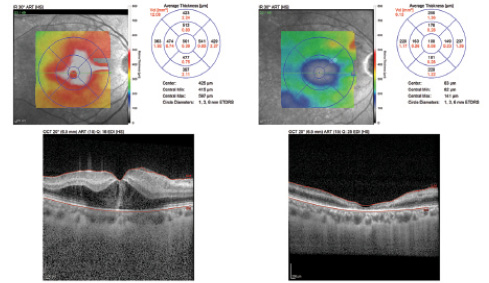

<p>Figure 1. Case No. 1: Accidental intravitreal injection of dibekacin. Patient had CME with count fingers VA. One month after intravitreal HCT injection, CMT decreased from 410 μm to 89 μm with no change in BCVA.</p>

Figure 1. Case No. 1: Accidental intravitreal injection of dibekacin. Patient had CME with count fingers VA. One month after intravitreal HCT injection, CMT decreased from 410 μm to 89 μm with no change in BCVA.